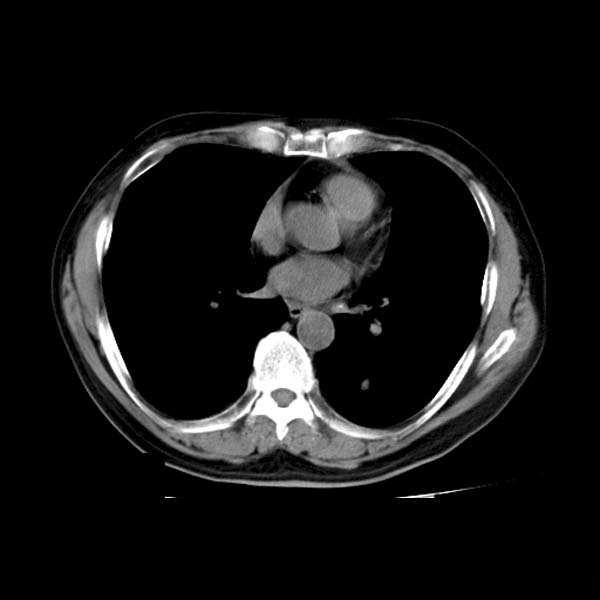

以下是引用守望可可西里在2008-6-24 1:11:00的发言:[br][br] 考虑为周围型肺癌:[br] 1.分叶结节,形态极不规则,蟹足样伸展的恶性浸润特征比较明确。[br] 2.磨玻璃影中由多个更高密度小结节聚集呈梅花瓣样。[br] 3.局部胸膜凹陷征比较明确。[br][br] 另:纵隔胸膜明显增厚、粘连。

以下是引用zjzjr在2008-6-24 11:19:00的发言:[br]支持左下肺周围型肺癌伴右肺转移,纵隔淋巴结转移,心包积液.

以下是引用zhangling在2008-6-24 14:56:00的发言:[br]我们科室意见报告为[br][br]1考虑左下肺周围型肺癌[br]2右肺小结节考虑转移瘤,纵隔淋巴结转移[br]3心包积液. [br] 各位老师分析的相当好 谢意[br]